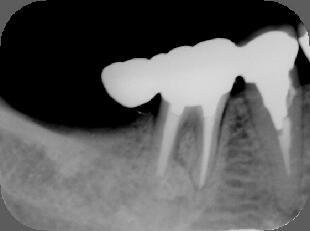

(2)初見では抜歯もしくは遠心根を抜去(ヘミセクション)を考慮しましたが、20代前半で

まだ若いため、約1年半をかけて根の治療を行いました。 ![]() ![]() ![]()

パノラマ画像:黒く写っている病巣が徐々に小さくなっていく様子が分かります。